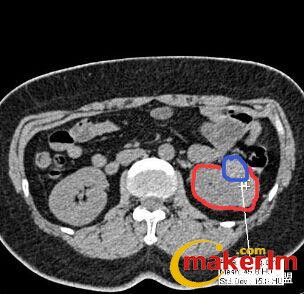

图为CT

某医院的外科医生需要做一个 3D 肾脏模型,但 CT 片拍出的二维图像中,其肿瘤位置只是通过灰色的色阶来表示(临床应用中称之为 CT 值),如上图中红色圈出来的是肾脏截面,蓝色则为肿瘤位置。从图中可以看出,在 CT 片子中蓝色部分仅仅比红色部分要白一点。这就导致肿瘤部分和正常部分难以准确区分。